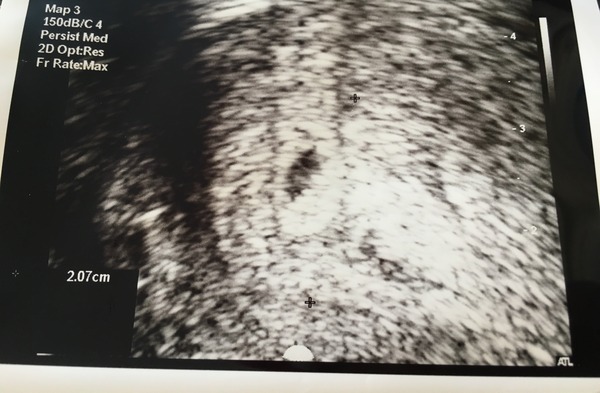

This is mine, like I said can not really see anything! But the measurement sounds similar to yours @bertiebotts, if that helps at all, as my dr wasn't worried with that for 4 weeks